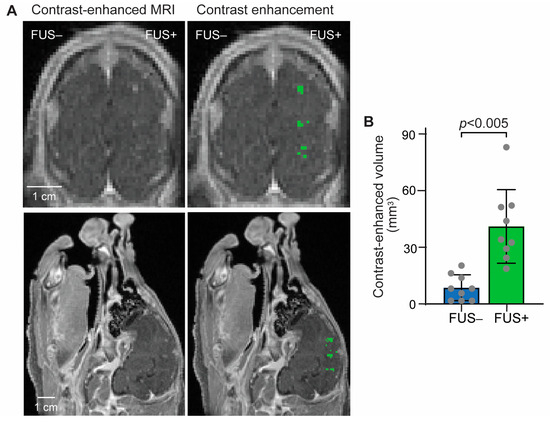

3.1. MRI Confirmation of FUS-BBBO